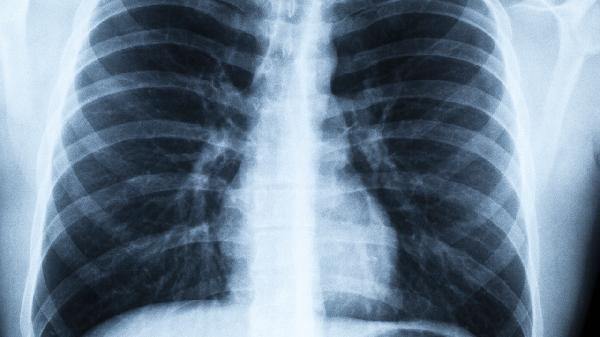

一、呼吸系统发出的危险警.报

1、持续性咳嗽

普通感冒咳嗽两周内会好转,但烟民特有的"烟咳"往往持续超过一个月。这种干咳常在夜间加重,严重时会出现金属音,这是支气管绒毛受损的表现。

2、呼吸音异常

安静时能听到自己呼吸带着哨音或喘鸣声,医学上称为"哮鸣音"。说明细小支气管已经出现狭窄,可能发展成慢性阻塞性肺病。